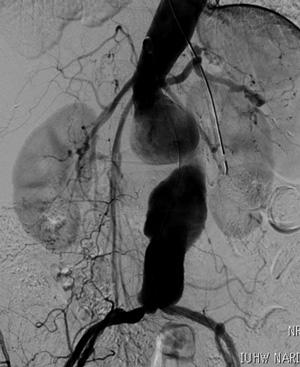

重症虚血肢に対するハイブリッド治療

腸骨動脈ステント(青矢印)・バイパス術(赤矢印)